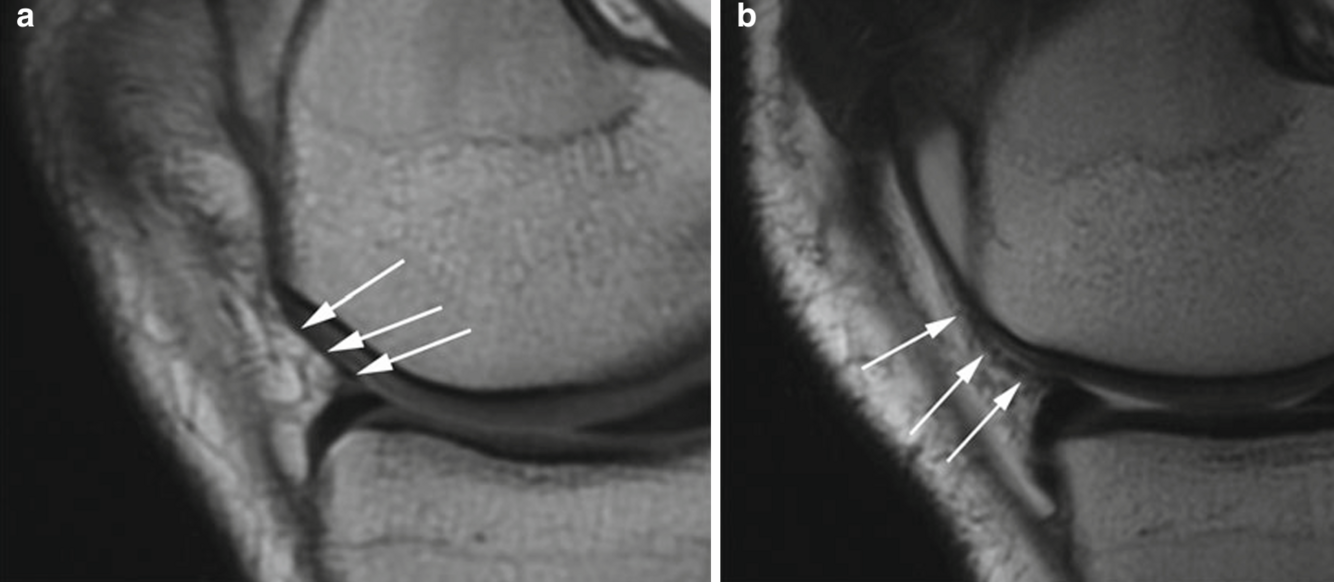

Fig. 5.3 Ligamento patelomeniscal. Las imágenes de FSE de densidad de protones sagitales (PD) en un hombre de 22 años ( a ) y una mujer de 19 años ( b ) muestran el ligamento patelomeniscal (flechas) anteriormente, conectando el menisco medial con el margen rotuliano. El ligamento es difícil de ver en una imagen. Por lo general, se necesita una vista dinámica de varias imágenes